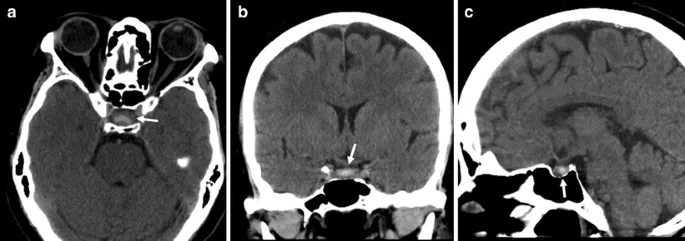

| Aneurysmal CN III | Pupil involved, headache | CTA/MRA | <6 hours | Neurosurgery |

| Pituitary Apoplexy | Bitemporal VF, endocrine | MRI pituitary | <24 hours | Steroids + surgery |